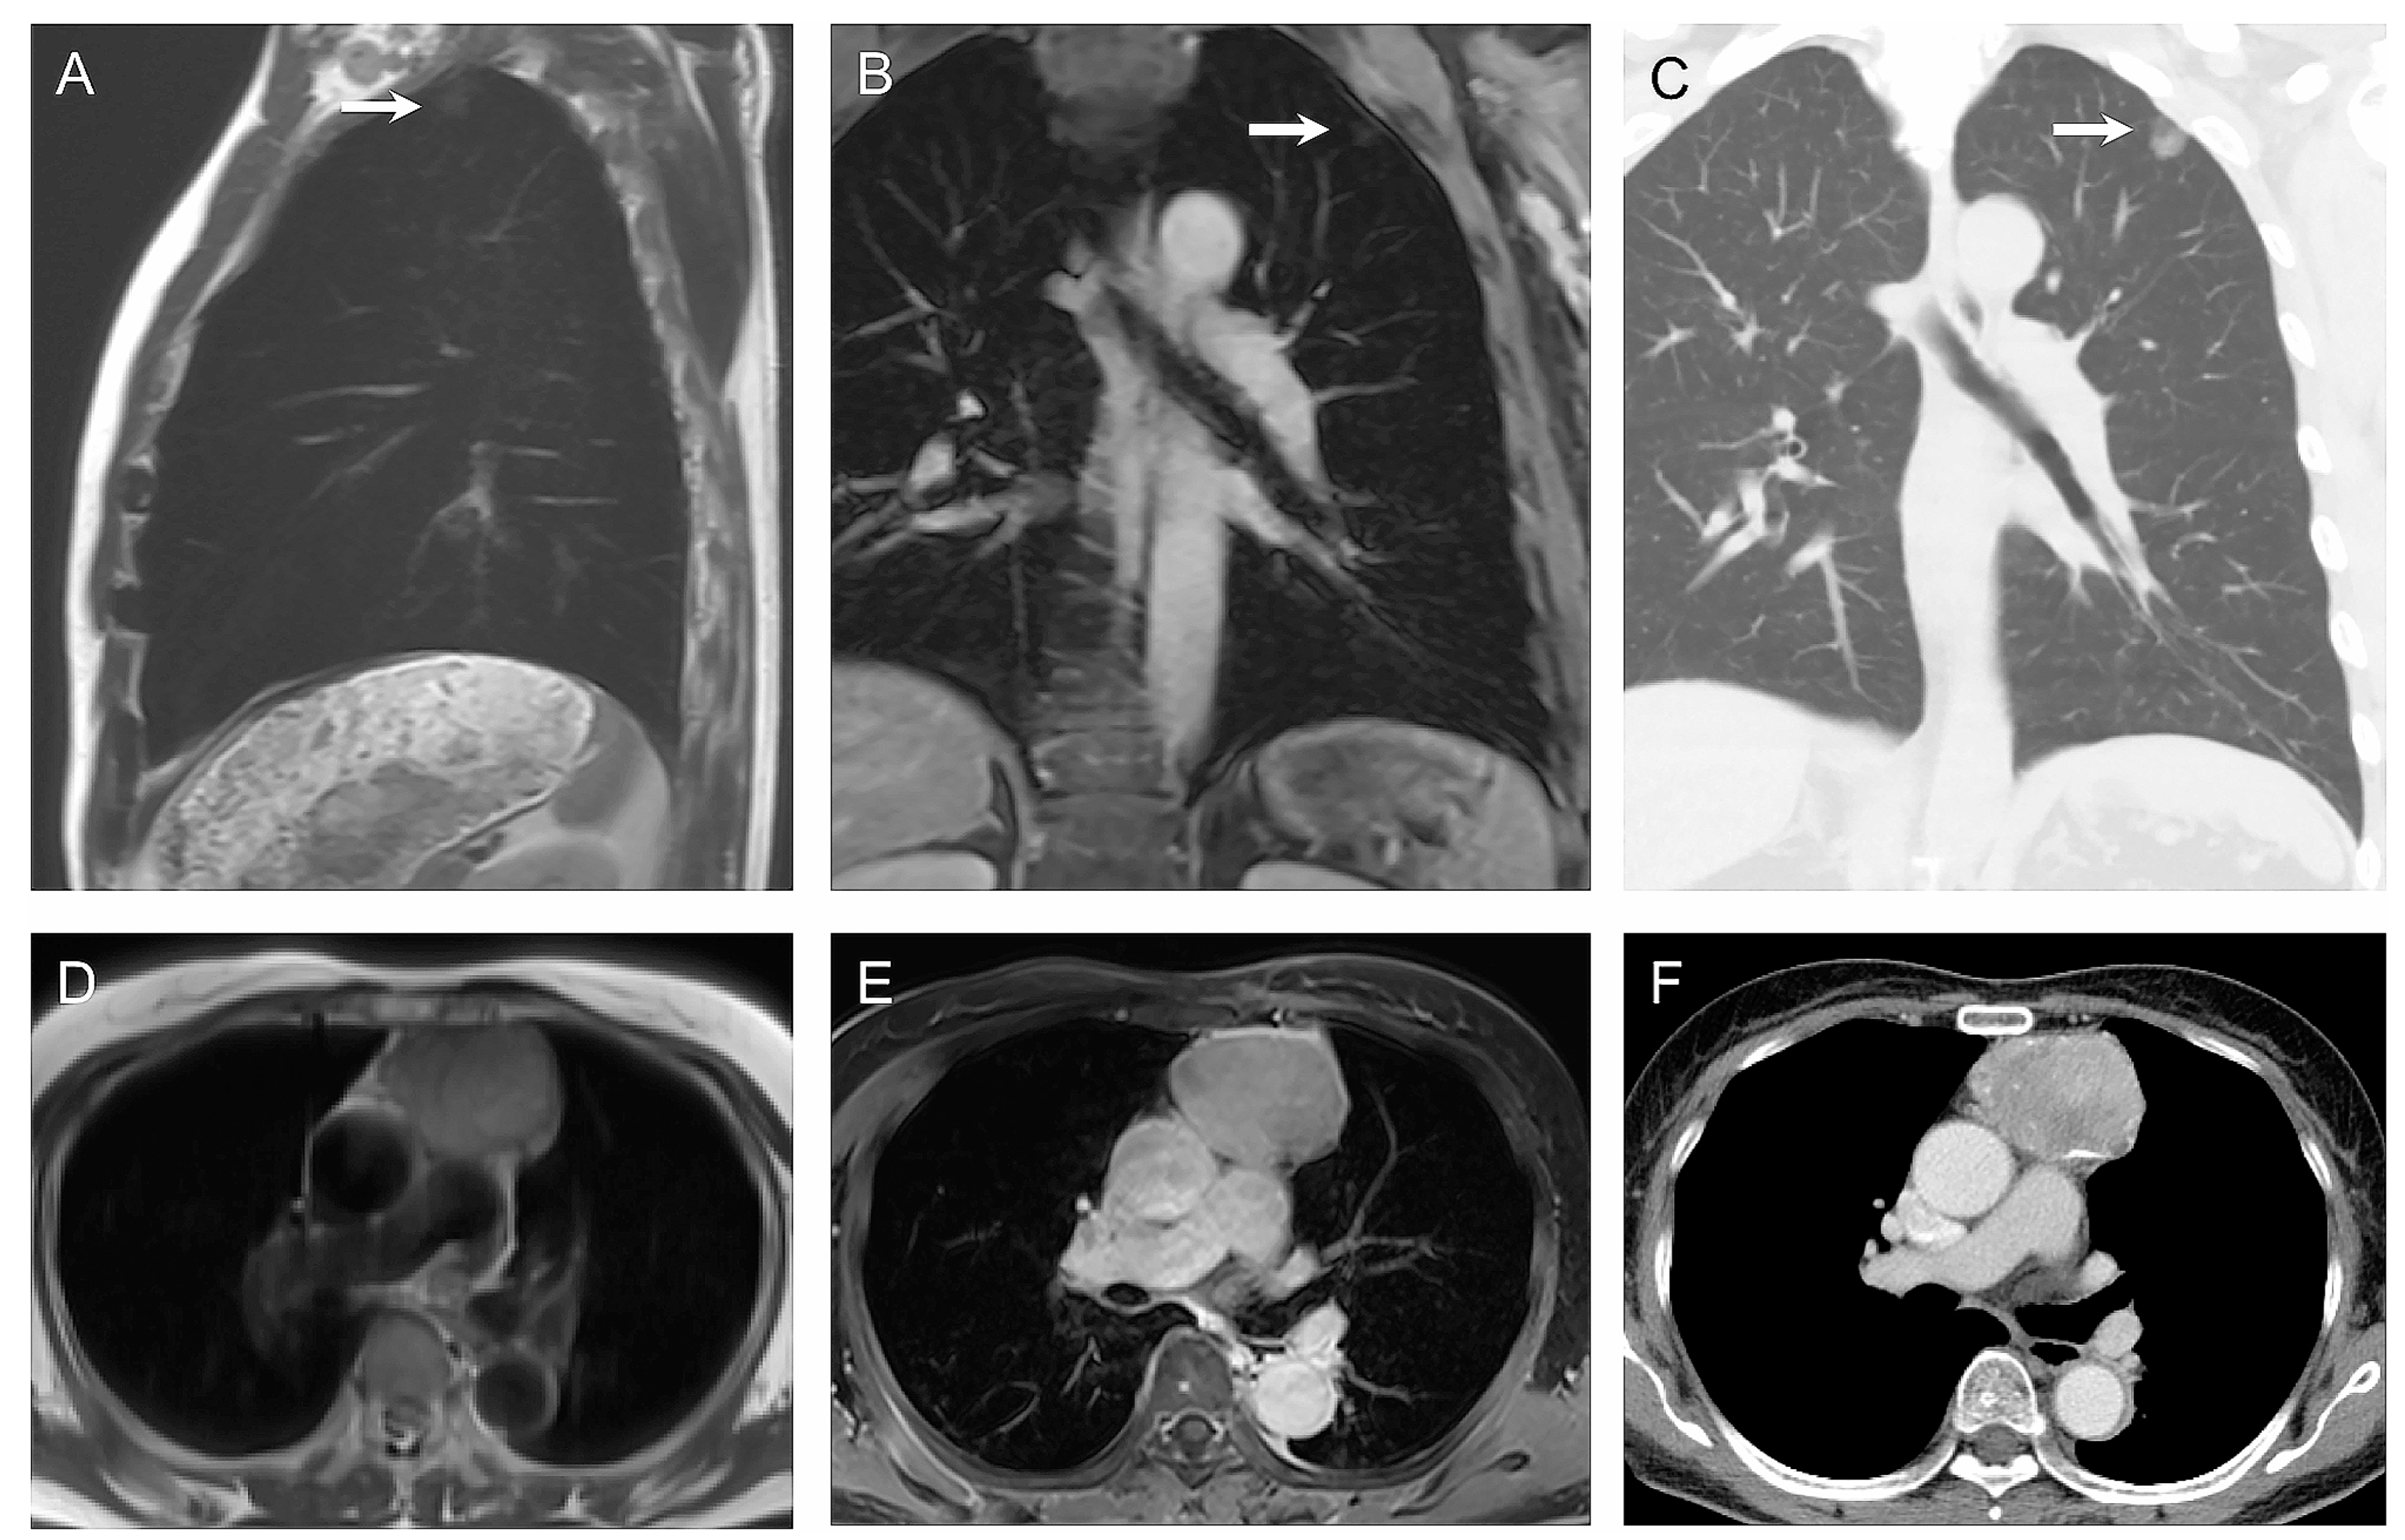

5. ONCO-RADS

- Petralia, G.; Koh, D.-M.; Attariwala, R.; Busch, J.J.; Eeles, R.; Karow, D.; Lo, G.G.; Messiou, C.; Sala, E.; Vargas, H.A.; et al. Oncologically Relevant Findings Reporting and Data System (ONCO-RADS): Guidelines for the Acquisition, Interpretation, and Reporting of Whole-Body MRI for Cancer Screening. Radiology 2021, 299, 494–507. [Google Scholar] [CrossRef]